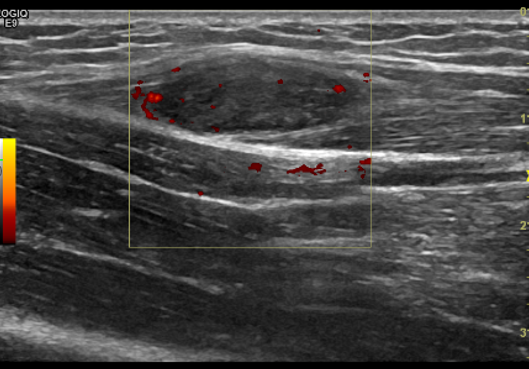

左侧前臂肌层可见低回声结节,大小约 2.3cm×0.8cm ,呈梭形,边界清楚,形态规则,回声欠均匀,可见少许血流信号(见图 1-2 )。

图 2 肿物能量多普勒图